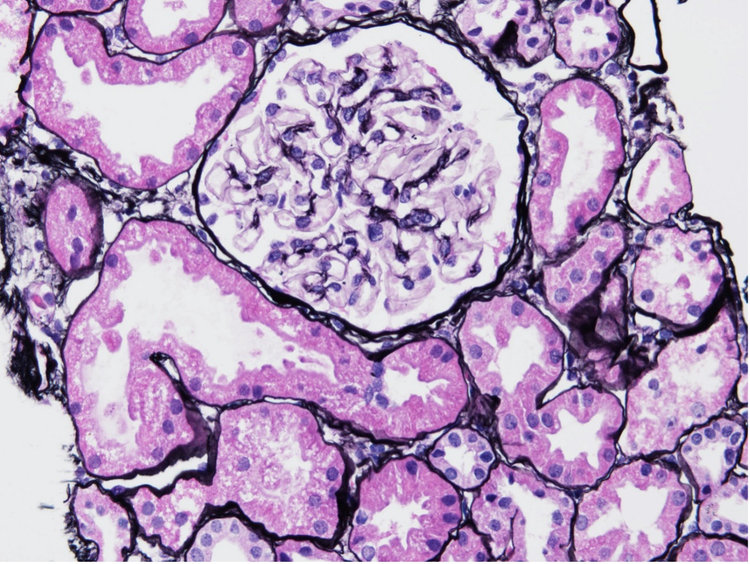

Abbildung 1 zeigt beispielsweise Nierenproben von Patienten mit LN der Klasse I im Frühstadium ohne signifikante glomeruläre Veränderungen im Vergleich zu gesunden Probanden. 2

Abbildung 1: Biopsie einer Niere mit LN der Klasse I, gefärbt mit Silberfärbung nach Jonas.